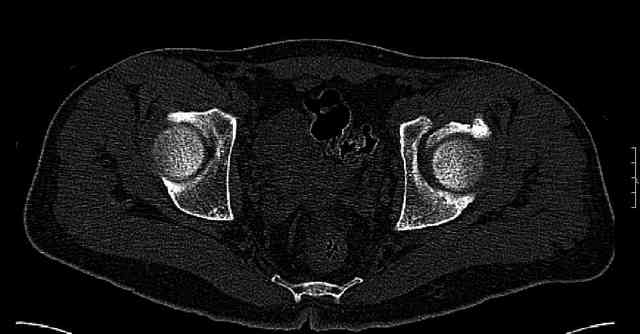

Some more images. Does it help to guess which part of the acetabulum is displaced?

Normal appearing SI joints and a healed posterior column limb... my bet's on caudal segment displacement.

Or you can just leave it... he has good dome coverage and it may be a durable hip for some time... maybe.

The posterior element is so minmally undisplaced. There is good congruence of the joint, and to top it all, 6 weeks have passed. If you consider ORIF now, I don't expect that much improvement could be accomplished. Not to mention the need for extensive approaches with their morbidity.

If you leave him alone now, and if the need arises in the future I believe that a standard THR would be good enough. And this is of course a much simpler procedure than the ORIF currently considered.